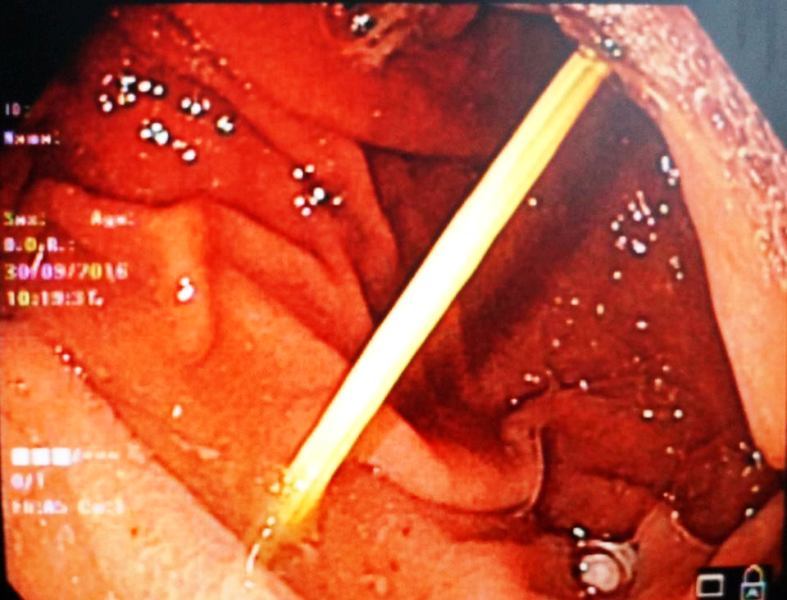

| BS gắp chiếc thìa từ trong dạ dày ra ngoài |

Tiến hành hội chẩn, các bác sỹ quyết định thực hiên phương pháp nội soi dạ dày gắp dị vật qua ống mềm cho bệnh nhân.

Sau 4 phút, các bác sĩ đã gắp thành công chiếc thìa ra khỏi dạ dày, sức khỏe bệnh nhân hoàn toàn bình thường và được xuất viện ngay sau đó.